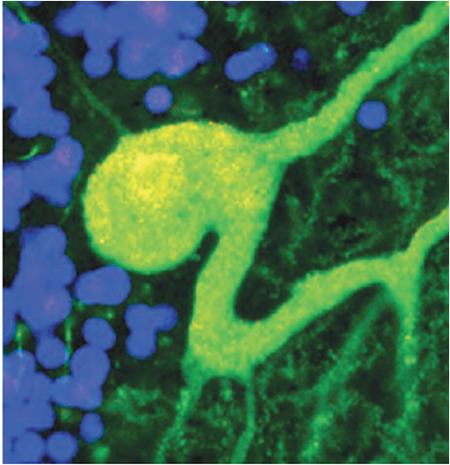

The brain is the overall control centre of appetite and energy expenditure, using interconnected neurological systems to assess and respond to changes inmetabolic state. University of Aberdeen medical scientists Professors Lora Heisler and Peter McCaffery and Doctors Mirela Delibegovic, Sandy Ross and Lynda Williams will discuss astonishing findings about how our brain controls what we eat and how the wrong nutrition can damage our brain and may contribute to Alzheimer’s disease.